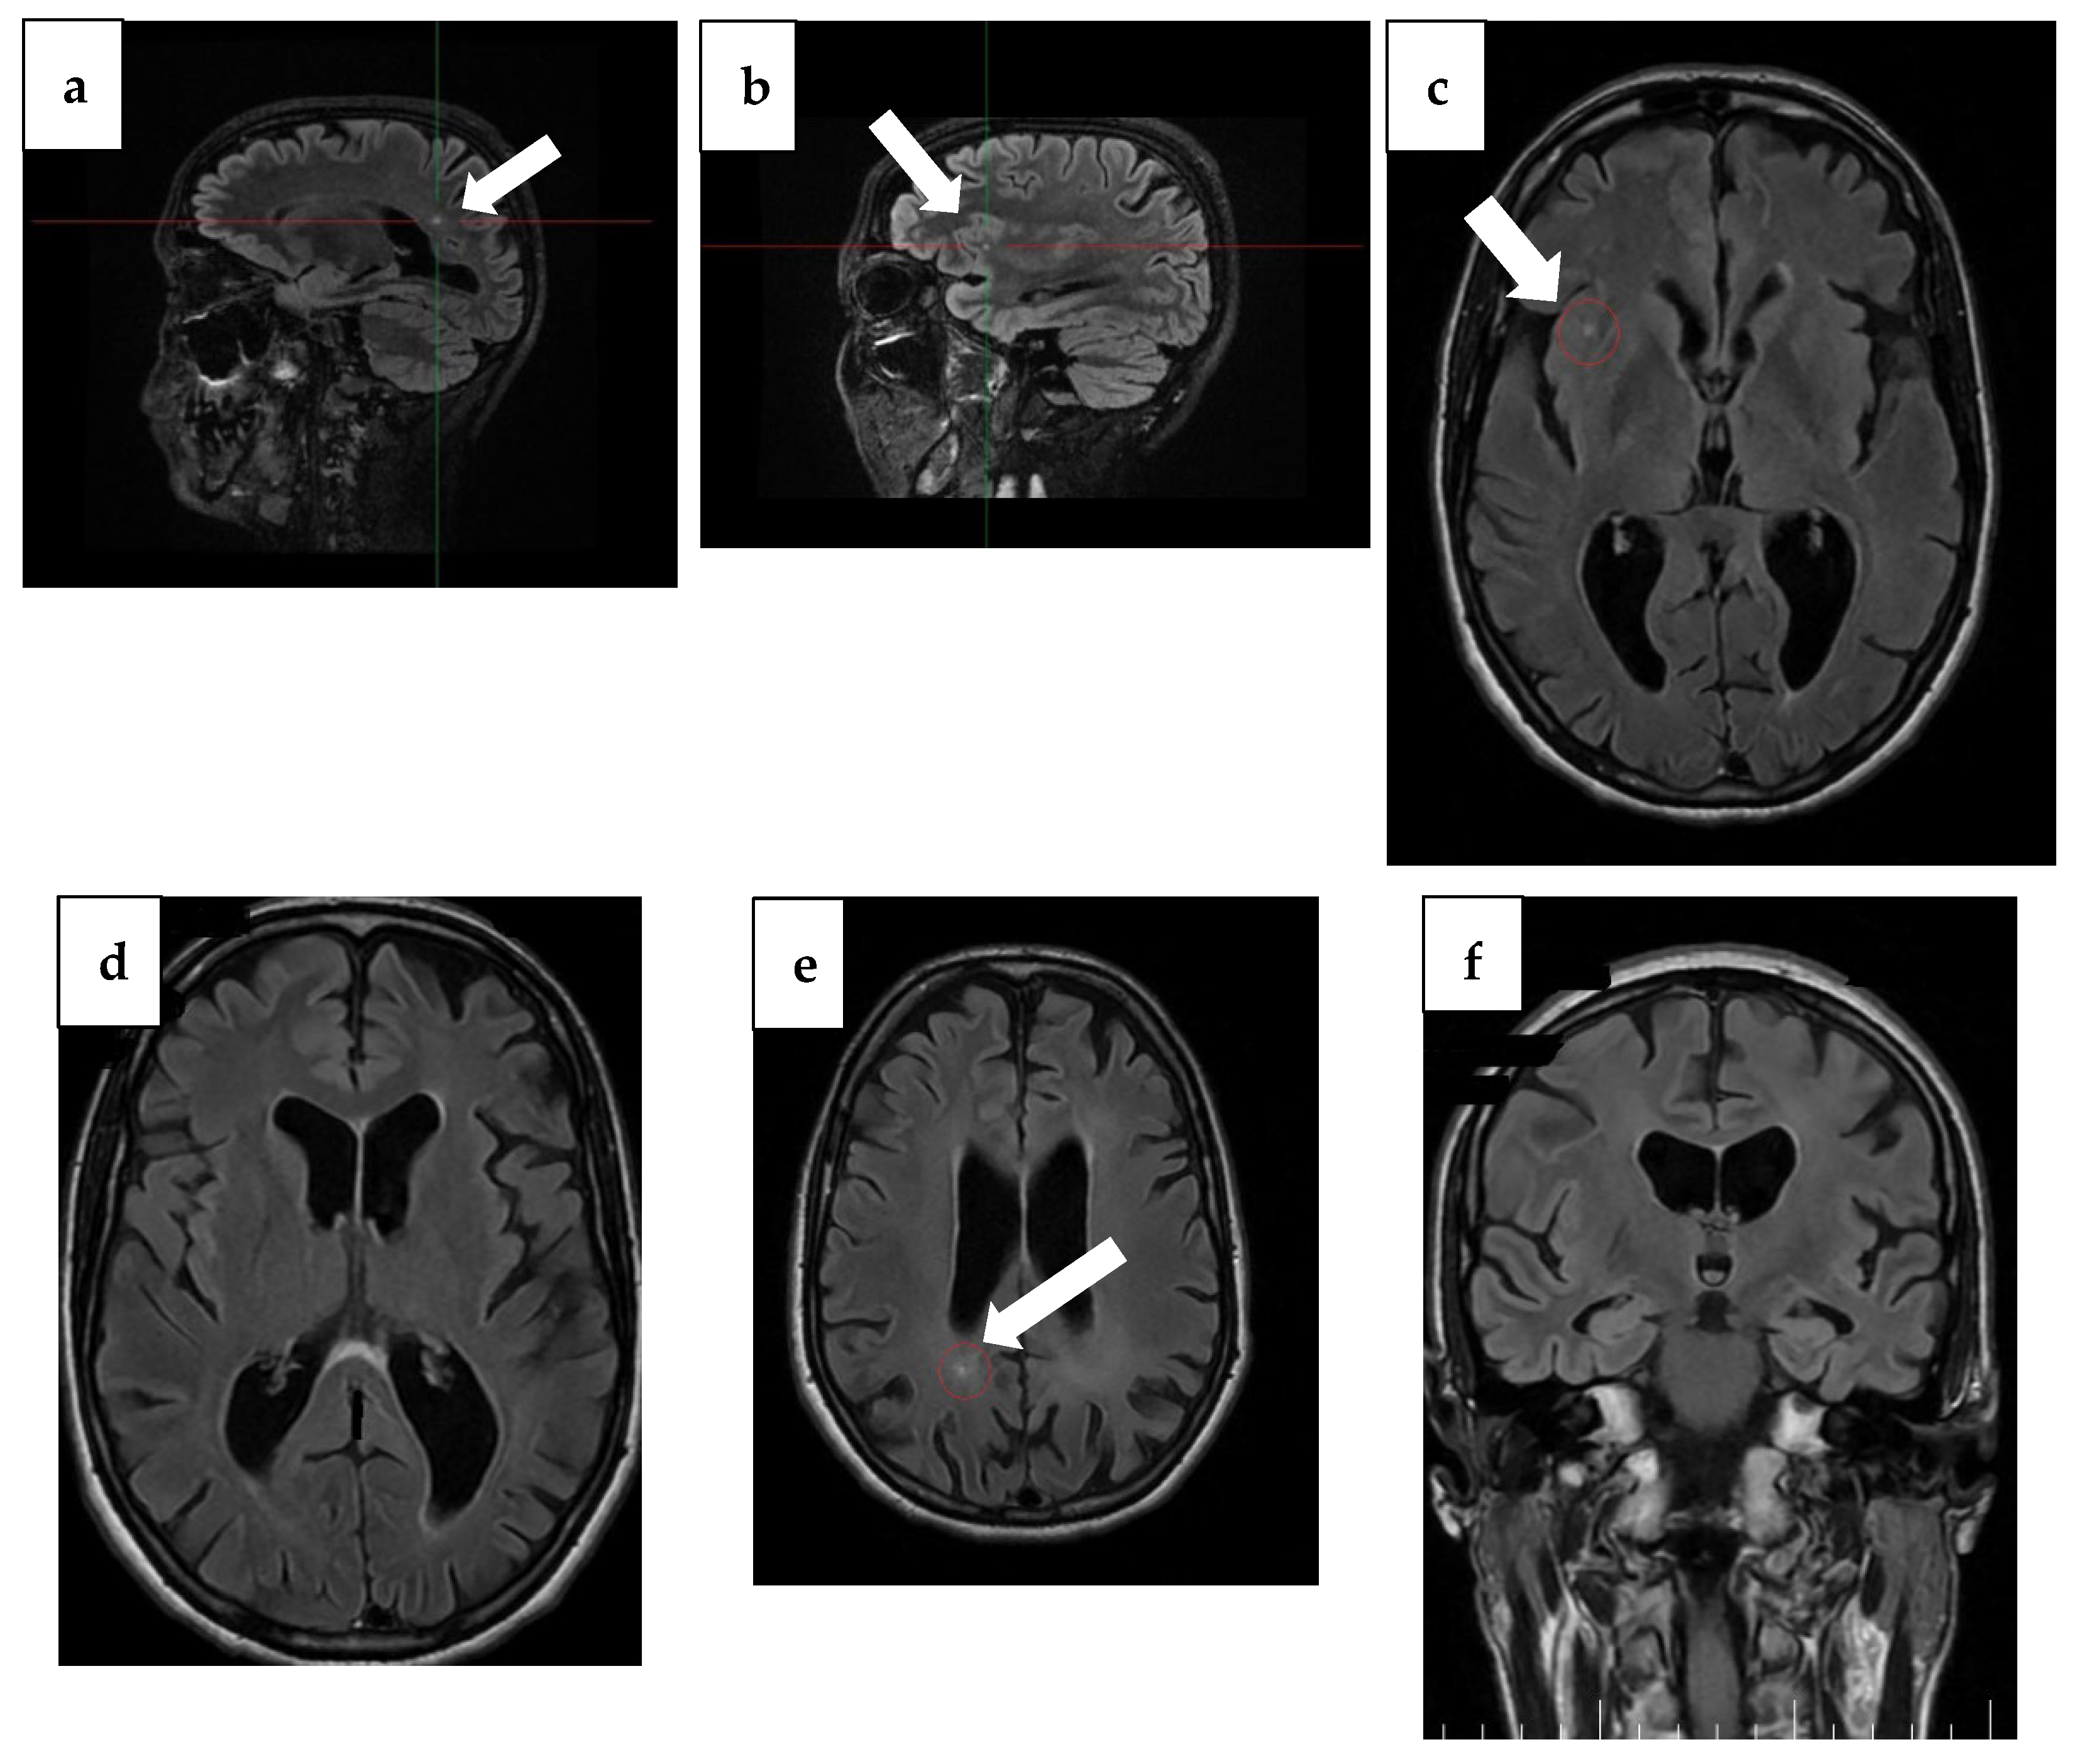

| Baseline (4 years ago) | MMSE 16/30 | Tau, p-Tau, Aβ42 within normal limits; 14-3-3 negative | Temporal atrophy; two punctiform FLAIR lesions (insula + occipital horn); ex vacuo ventriculomegaly | Initial cognitive decline after vestibular neuritis; onset of disorientation and working memory/language deficits |

| Year 1 (3 years ago) | MMSE 16/30 | Not repeated | Progressive cortical/subcortical atrophy; lesions unchanged | Dependence increasing, moderate neurocognitive disorder |

| Year 2 (2 years ago) | MMSE 12/30 | Not repeated | Parietal atrophy becoming evident | Rapid decline, moderate-to-severe impairment |

| Year 3 (1 year ago) | MMSE 9/30, MoCA 4/30 | Tau ↑ 877 pg/mL; p-Tau ↑ 63.6 pg/mL; Aβ42 ↓ 0.94 | Hippocampal atrophy (MTA score 2); parietal atrophy (Koedam 2); severe corpus callosum thinning with splenium demyelination (T2/FLAIR hyperintensity, T1 hypointensity) | Severe cognitive disorder requiring permanent care; anxiety and depression prominent |

| Year 4 (Current) | Severe impairment, no formal testing | Not repeated | Global progression of atrophy; no new lesions | Severe apathy, hypersomnia, total dependence, high wandering risk |